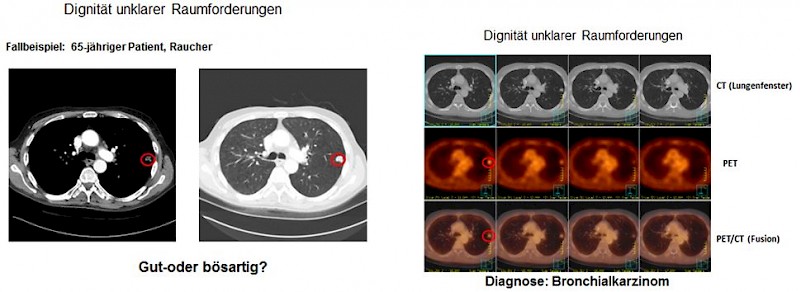

Die PET-CT gilt als eines der genauesten Diagnoseverfahren in der Tumordiagnostik. Mit ihr kann man kleinste Tumorherde und Metastasen in einer einzigen Ganzkörperuntersuchung erfassen und lokalisieren.

Die PET-CT ist zusätzlich ideal zur Kontrolle des Therapieverlaufs bei einer bestehenden Tumorerkrankung, aber auch zur Früherkennung von Tumorerkrankungen geeignet. Bei der Nachsorge kann mit einem Blick geklärt werden, ob Metastasen vorhanden sind oder nicht.

F-18-FDG (F18-Desoxyglukose), ein mit radioaktivem Fluor markiertes Traubenzuckermolekül. ist das weitverbreitetste Radiopharmakon und wird hauptsächlich in der Onkologie eingesetzt. In der Tumordiagnostik mit FDG macht man sich zunutze, dass Krebszellen, deren Wachstum entreguliert ist, einen deutlich erhöhten Traubenzuckerverbrauch gegenüber gesunden Zellen haben. Im späteren PET-Bild hebt sich der Tumor dadurch ganz deutlich vom umliegenden, gesunden Gewebe ab, weil sich das FDG in Tumorzellen anreichert.

- Bronchialkarzinome